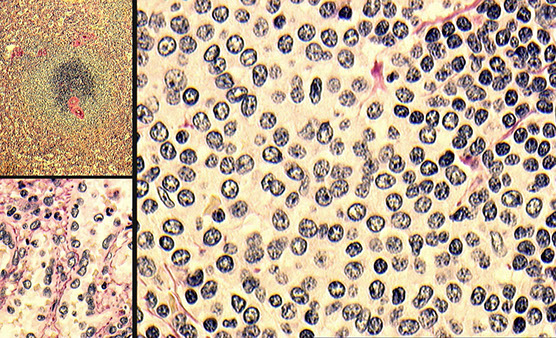

Upper left shows scattered reactive follicles, upper right shows fairly well-differentiated mantle zones, lower left shows aggregates of monocytoid B-cells (small cells) in the paracortical region, and the lower right is a somewhat atypical immunoblastic cells (would stain positive for EBV ISH)

High-powered view of monocytoid B-cells (MBCs) in infectious mono, which have slightly irregular, almost centrocyte-like nuclei with abundant pale cytoplasm and some interspersed neutrophils

Infectious mononucleosis. Admixed population of cells of varying sizes. In areas where immunoblasts predominated (right) which could be a florid expansions, like large aggregates or sheets of cells with mitotic activity. Spend some time on low power to appreciate the normal architecture, try to find areas with a variety of cell types. Immunoblasts may resemble Reed-Sternberg (RS) cells (inset). [3]